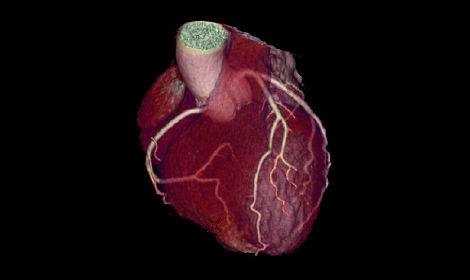

Automatisierte Nachverarbeitungswerkzeuge

Revolution Ascend vereinfacht die Nachverarbeitung durch Prospective Multiple Reconstruction, automatisierte Neuformatierungen und eine Reihe intelligenter Anwendungen, die eine hohe Effizienz und hochwertige CT-Bildgebung in allen klinischen Bereichen ermöglichen.

Funktionen für die Herz-CT-Nachverarbeitung

• SnapShot Freeze 2 ist ein automatischer Bewegungskorrekturalgorithmus für das gesamte Herz bei einer effektiven zeitlichen Auflösung von 29 ms*

• Automatisierte Nachbearbeitungsanwendungen für die Koronaranalyse und den Kalzium-Score ermöglichen es, Bilder direkt an der Konsole oder an der sekundären Bildbefundungsstation zu lesen

GEHCEffortlessWorkflowPost-scanImage2